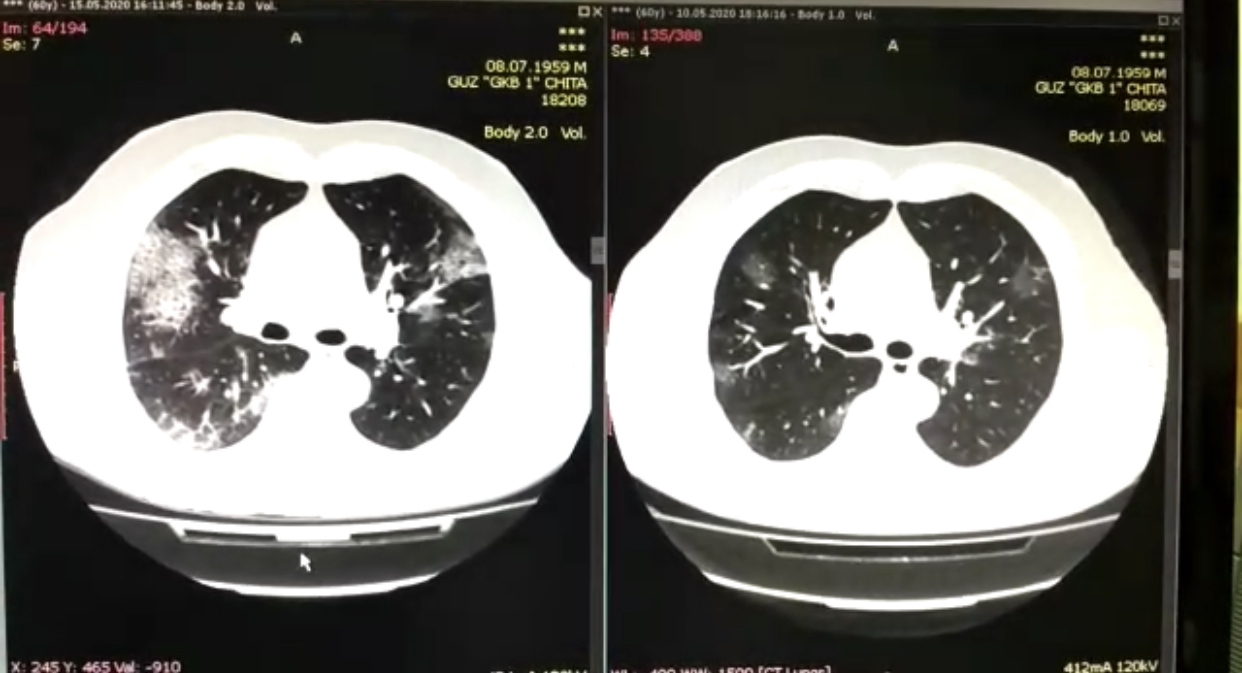

Часть вторая: очаги за несколько дней расползаются до тотальных размеров «Мужчина 60 лет поступает в моностационар. Самочувствие его вполне удовлетворительное. Из симптомов – кашель, высокая температура. Компьютерная томограмма показала начальные признаки поражения лёгких. Мы внимательно наблюдаем за пациентом. Назначаем лечение. Ежедневно оцениваем его состояние. Но на 5-ый день, несмотря на проводимую терапию, еле видимые участки "расползлись" до больших размеров и лёгкие тотально поражены», - рассказывает доктор.

На фото изображены легкие пациента. Слева - белые очаги, поразившие легкие. На снимке справа – его же легкие ещё пять дней назад, где просматривались лишь небольшие поражения.